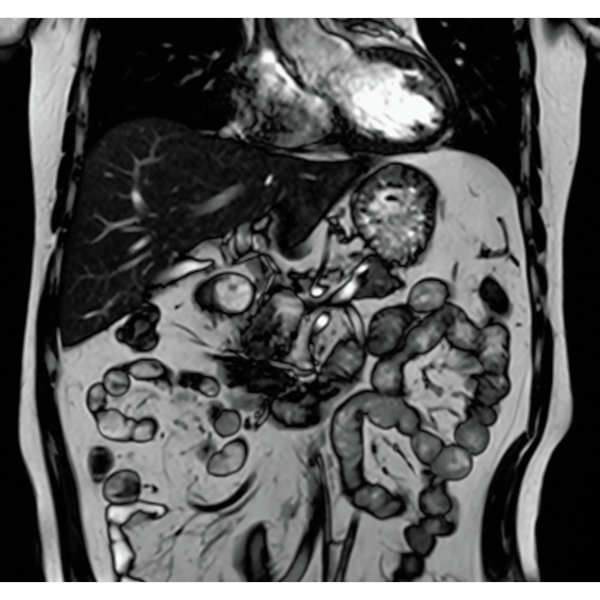

IP-RAPID×DLR Plusは撮像時間の短縮も可能なため、同一検査時間であれば、より多くの撮像が可能となります。従来検査に対して、異なる画像種類や断面など、追加撮像によって情報量を増やすことができ、診断をより確かなものに。

IP-RAPID×DLR Plusによって呼吸同期計測や横隔膜同期計測など時間のかかる検査を短くできます。さらに時間を短くし、息止めによる検査に変更することもでき、患者さまの状況に合わせて検査をお選びいただけます。選択肢が増えるので、検査の幅が広がります。

IP-RAPID×DLR PlusはVolumeScanやRadialScan、HalfScanといった基本撮像に加え、MultiContrastScanのFatSepやDWIなど多くの撮像法でお使いいただけます。広範囲DWIやWhole Spine撮像など時間のかかるWide Scanにも併用でき、多くの部位で従来よりも詳細な情報を得ることができます。

撮像データに生じたアーチファクトを除去・抑制したり、限られた撮像データから再構成画像を生成する機能を提供することで、再撮像率を低減し、スムーズなMRI検査の実現をサポートします。